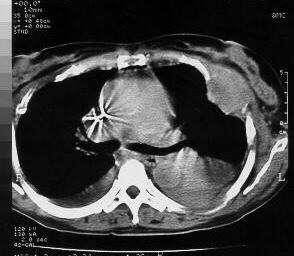

Chest CTs demonstrating the left thoracic wall mass, with intra-thoracic involvement, and costal arch destruction.